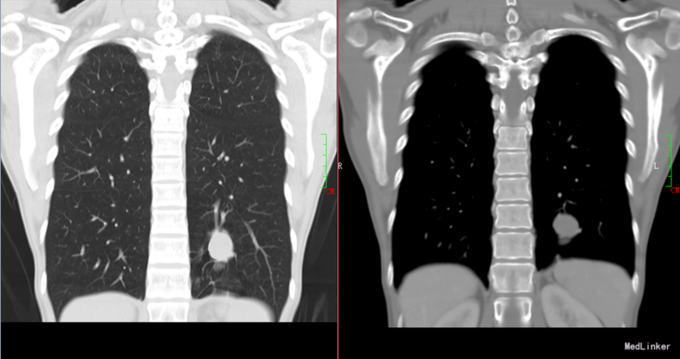

患者女性,33岁因体检发现左下肺肿物8天入院,患者无不适,既往史无特殊。

查体:未见明显异常。 辅查:我院胸部CT示:左肺下叶后基底段结节,良性可能,建议进一步检查。

入院诊断:左肺肿物。入院后行胸腔镜下左肺肿物切除术,术中见肿物位于左肺下叶后外侧段脏层胸膜下,大小约20×30×20mm,质软,囊性,边界清,表面胸膜未见凹陷,遂楔形切除左下肺外侧段肺组织,完整切除肿物。标本纵行切开可见肿物囊性,囊性液体为巧克力样。术后病理:支气管管壁纤维性增厚,伴慢性炎症细胞浸润,周围肺组织肺泡扩张,伴水肿。病变符合支气管扩张症改变,符合支气管闭锁。